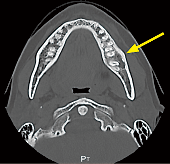

左側下顎部の激痛 17 5月号1ans 診断力てすと Dental Diamond デンタルダイヤモンド